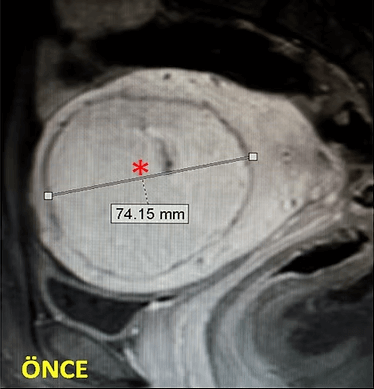

37 yaşında, kansızlık, gaz, sık idrara çıkma şikayetleri ve hamilelik arzusu var. Miyomektomi önerilmiş, ancak operasyonda rahimin alınabileceği söylenmiş. Emar’da tek, dev bir miyom (*) mevcut. Tek seans perkütan ablasyon sonrası miyomun belirgin küçüldüğü izleniyor. İşlemden 2 yıl sonra hasta hamile kalmıştır.